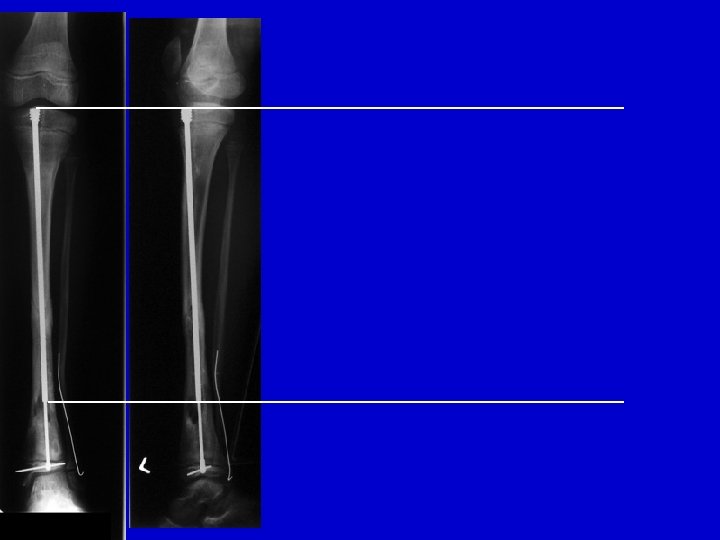

Treatment Type III • Closed distraction + compression • Gradual deformity correction • ± Lengthening • ± IM Rod (late)

distraction of CPT follow-up

pre-op compression healed